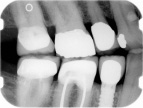

Radiographically, a dental implant looks like this:

Implant in bone Implant with crown attached

Here is an example of a single dental implant, where there are other missing teeth.